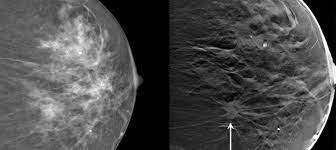

What Does Breast Cancer Look Like On A 3D Mammogram : Mammography 3d Mammography Tomosynthesis Densebreast Info Inc : Macrocalcifications, which look like small white dots on a mammogram.. To license this video for patient education or content marketing, visit: The doctor reading your mammogram will be looking for different types of breast changes, such as small white spots called calcifications, larger abnormal areas called masses, and other suspicious areas that could be signs of cancer. This overlapping tissue can cause the resulting image to look like cancer. Microcalcifications, which look like white specks on a mammogram. The tumor cells don't stay within the clear borders of the mass, but instead invade the nearby breast tissue.

Bright spots on a mammogram that look like potential tumors could turn out to be overlapping tissues or a blood vessel folding over on itself, friedewald said. American cancer society, 9 oct 2017. One advantage of ultrasound technology is that it allows substantial freedom in obtaining breast images from any orientation. Specialist doctors (radiologists) trained to interpret mammograms can identify any abnormal areas, masses or calcium. The outer edges of these cells look fuzzy or spiky (called spiculated).

Essentially, mammograms turn a 3d object into a 2d object. This is why you should always talk to your doctor if you notice an unexplained change in the size of a breast. What does the doctor look for on a mammogram? cancer.org. A screening mammogram is performed at regular intervals to check for breast cancer in women who have no signs or symptoms of the disease. Bright spots on a mammogram that look like potential tumors could turn out to be overlapping tissues or a blood vessel folding over on itself, friedewald said. To license this video for patient education or content marketing, visit: What does breast cancer look like? This overlapping tissue can cause the resulting image to look like cancer. Finding breast lumps and seeing change in the size and shape. Screening mammograms have been used since the 1980s. Digital breast tomosynthesis (tomo), also known as 3d mammography, is a revolutionary new screening and diagnostic breast imaging tool to improve the early detection of breast cancer. Ultrasound characterization of breast masses. indian journal of radiology and imaging. Calcifications are calcium deposits within the breast tissue and they look like small white spots.

More Breast Cancers Detected With 3d Mammography National Breast Cancer Foundation Nbcf Donate Online from 1o2l7w1aqqrk1f987e40vzis-wpengine.netdna-ssl.com This overlapping tissue can cause the resulting image to look like cancer. Several patterns of calcifications are seen with dcis, including: The look of breast cancer on a mammogram a tumor or lump will appear as a focused white area on the mammogram. Most screening mammograms include two views of each breast taken from different angles. Specialist doctors (radiologists) trained to interpret mammograms can identify any abnormal areas, masses or calcium. What does breast cancer look like on a mammogram? A tumor that is benign, it is not a health problem and it may not grow or change shape. Ultrasound characterization of breast masses. indian journal of radiology and imaging.

Breast cancer and some noncancerous (benign) breast conditions can appear white on a mammogram. This overlapping tissue can cause the resulting image to look like cancer. Diagnostic mammograms involve taking more views than screening mammograms. It's so important to listen to the messages our bodies are telling. A number of studies have found that 3d mammograms find more cancers than traditional 2d mammograms and also reduce the number of false positives. Ultrasound characterization of breast masses. indian journal of radiology and imaging. Even if you have a lump in only one breast, pictures will be taken of both breasts. Finding breast lumps and seeing change in the size and shape. 1 the gray areas correspond to normal fatty tissue, while the white areas are normal breast tissue with ducts and lobes. A false positive is when a mammogram shows an abnormal area that looks like a cancer but turns out to be normal. Breast cancer can appear as a spiculated mass, cluster of tiny calcifications, smoothly marginated mass, area of subtle distortion or be invisible on. Macrocalcifications, which look like small white dots on a mammogram. One advantage of ultrasound technology is that it allows substantial freedom in obtaining breast images from any orientation.